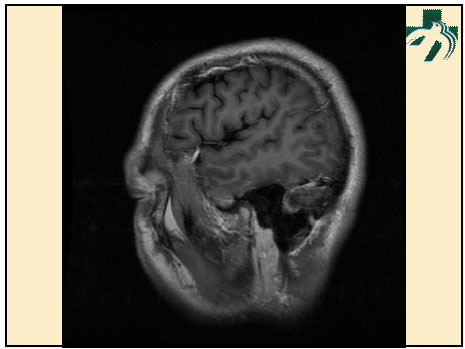

奴卡氏菌感染

第九期三博

读片会

病例之四

北京协和医院 提供

男性,22岁。自觉虫咬后皮疹、肢体麻木4月